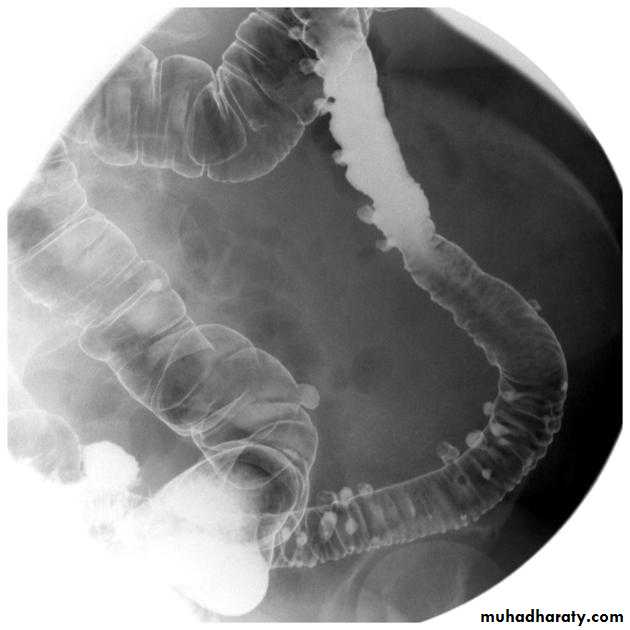

Barium small bowel follow-throughfindings of CD

Multiple mucosal ulcers aphthous ulcerslongitudinal fissures

Multiple skip lesions

when severe leads to cobblestone appearance

may lead to sinus tracts and fistulae

widely separated loops of bowel due to fibro-fatty proliferation

thickened folds due to edema

Pseudo diverticula formation: due to contraction at the site of ulcer with ballooning of the opposite site